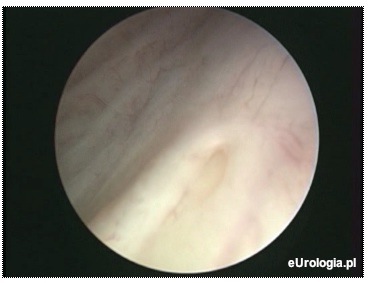

Fot. Ujście lewego moczowodu widoczne w czasie cystoskopii.